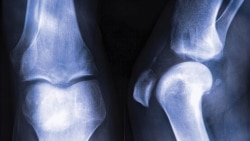

This x-ray shows osteoporosis in a leg joint.

Osteoporosis literally means "porous bones." Normal bones have many tiny holes. With osteoporosis, the bones become so thin in places that even a simple stretch or a cough can result in a bone fracture.